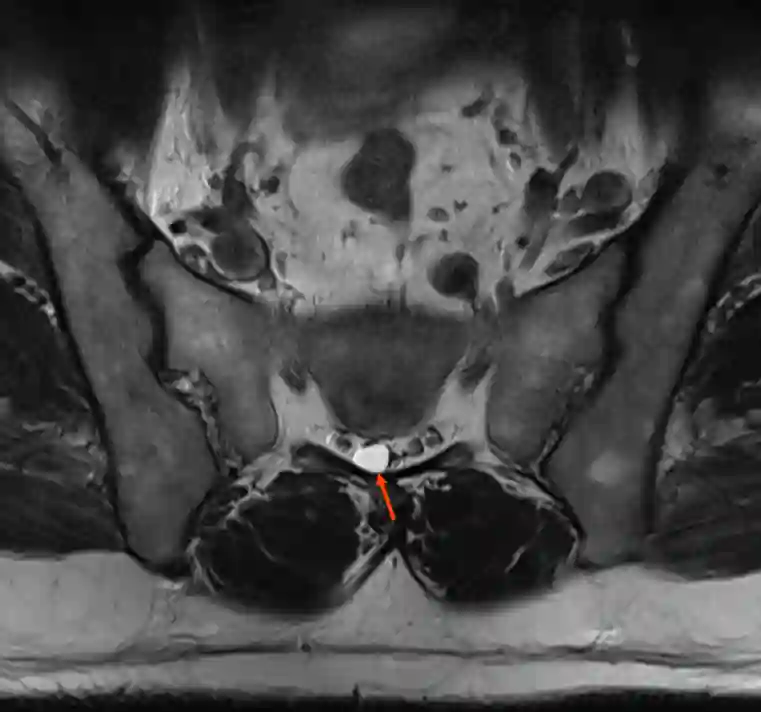

Tarlov cyst on MRI

Illustration of a right-sided Tarlov cyst (red arrow) in the axial T2 MRI image.